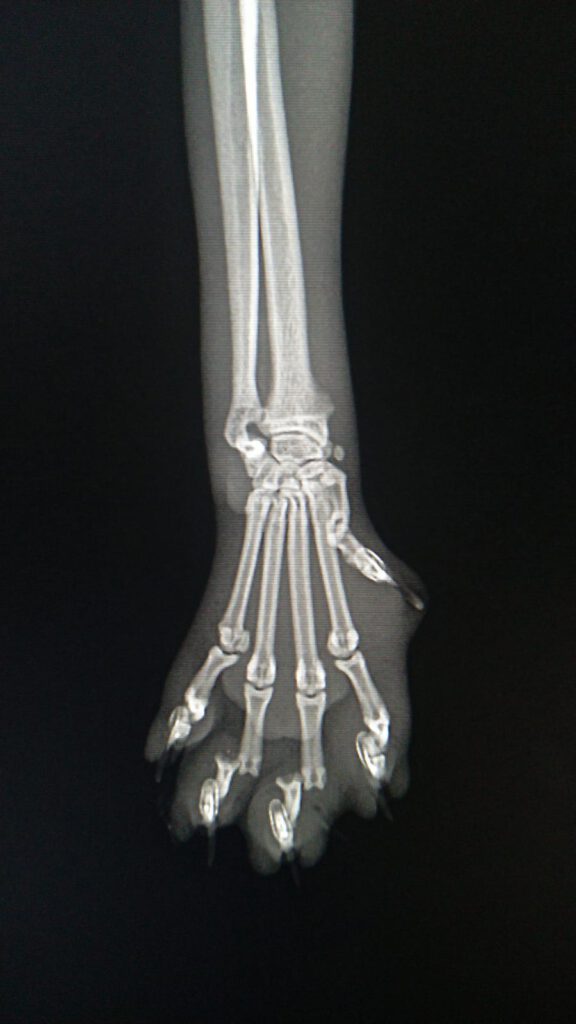

In der anschließenden Behandlung stellte sich heraus, dass die Katze neben erheblichen Verletzungen an der Pfote auch metallische Gegenstände, vermutlich die Befestigung des Köders, in Körper hatte. Die Veröffentlichung der Röntgenbilder wurden vom Tierarzt genehmigt.